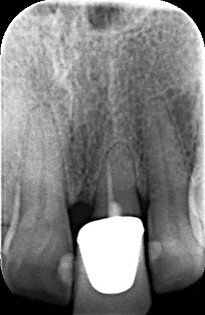

Normally, the first radiographic examination performed is an intraoral radiograph for a single tooth (Fig. 1) or a dental panoramic tomogram if the need for a more extensive treatment is suspected. In the same session, both dental arches are scanned with an intraoral scanner and the bite is registered. A simple photographic sequence is followed:

The female patient, aged 47 and a non-smoker, was in good general health. She performed regular oral hygiene and had good periodontal health. The patient experienced increasing mobility of the maxillary left central incisor and complained about compromised aesthetics due to the extrusion and progressive migration of the tooth in a buccal direction. The incisor had been treated with a crown at a preadolescent age after a violent trauma. The intraoral radiograph showed incomplete root development and evidence of a root canal therapy suggesting a strip perforation though no signs of periapical lesions were present. The shape of the crown was not symmetrical in relation to the triangular shape of the maxillary right central incisor, but had a wider and rectangular profile. Minor general gingival recession had led to the presence of a tiny inter-dental space. The marginal gingiva was reddened, and the central papilla was not symmetrical.

Probing depths were within 2 mm for both the right and left central incisors and the radiographic mesial and distal bone peaks were of a regular height.

It became evident that the short-rooted tooth could be extracted without compromising the buccal bone, and that there was sufficient bone volume and quality to obtain good primary stability of the implant. Thanks to the AIS 3D App software, this information can be visualised using the bone density tool and linear measures tool (Fig. 10c) and represented in a graphic or according to a coloured scale. The presence of the nasopalatine duct prohibited ideal palatal positioning of the implant, and if the implant were to be placed flush with the palatal alveolar bone, this would have resulted in a 1.5–2.0 mm high exposure of the implant collar on the buccal aspect (Fig. 11b). This information, combined with the aesthetic analysis, led to the decision to place the implant in that position and to augment the buccal bone volume with a contemporaneous GBR procedure, thus also providing for major soft tissue support. As often described in the literature, it is to be expected that in some measure the implant will deviate buccally2–4 from the original planning because of the major mechanical resistance of the palatal plate. The author’s team prefers whenever possible screw-retained solutions. Several production centres are capable of milling angulated screw access holes in cobalt-chromium abutments of up to 25°,5 which is a range that covers most cases in daily practice. It can be easily checked in the implant planning software whether the future access hole will exit on the palatal aspect of the tooth, either by angulating the implant extension tool or by choosing a virtual abutment from the library. Confirming being in the safety range from this point of view allowed for an approach that foresaw the implant in native bone without the necessity for major GBR on the apical aspect of the implant. Knowing that a flap needed to be raised to facilitate the marginal tissue augmentation, it was decided to use a surgical guide (Figs. 11c) for only the first drill to determine with precision the position and angulation of the osteotomy that would be performed freehand thereafter. In order to limit surgery time and eliminate unpredictable factors inherent in immediate loading, a removable temporary prosthetic tooth was produced in advance.